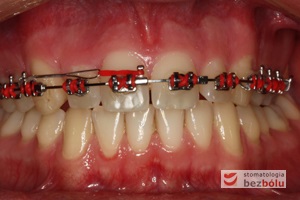

Młody 28-letni, pogodny, stale uśmiechnięty pacjent zgłosił się celem korekcji wad zębowych ograniczających pełną ekspresję uśmiechu. Głównym problemem był dodatkowy siekacz boczny (dwójka) po stronie prawej w łuku górnym. Dodatkowy ząb spowodował stłoczenia pozostałych zębów w łuku górnym oraz przesunięcie linii pośrodkowej. Obliczenia dostępnego miejsca dla siekacza bocznego wpłynęły na wybór zęba przeznaczonego do ekstrakcji. Usunięto dwójkę ustawioną dowargowo, zaś jej „siostrę bliźniaczkę” skierowaną w stronę podniebienia wprowadzono do łuku zębowego w drodze leczenia ortodontycznego. Problemem było szczelne zamknięcie szpary poekstrakcyjnej z powodu nadmiaru miejsca w kości. Wyrównano linię pośrodkową. Leczenie przeprowadzono jednym łukiem ortodontycznym górnym, dolny łuk zębowy nie wymagał założenia aparatu. Po zdjęciu zamków korekcję detali przeprowadzono z użyciem pozycjonera wykonanego w technice termoformingu. Stabilizację efektów leczenia zapewnił stały retainer klejony do powierzchni podniebiennych siekaczy górnych.

Leczenie ortodontyczne: planowanie i aktywna faza leczenia, leczenie retencyjne – lekarz stomatolog Magdalena Żywicka i lekarz stomatolog Marta Pakuła